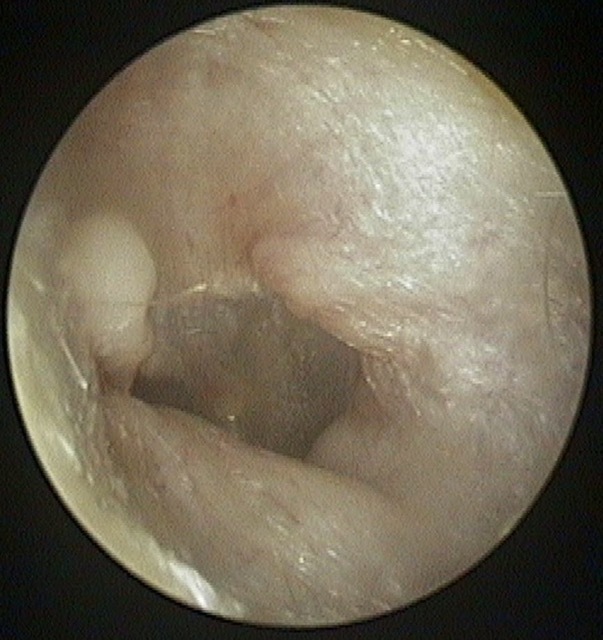

Atelectasis/Retraction